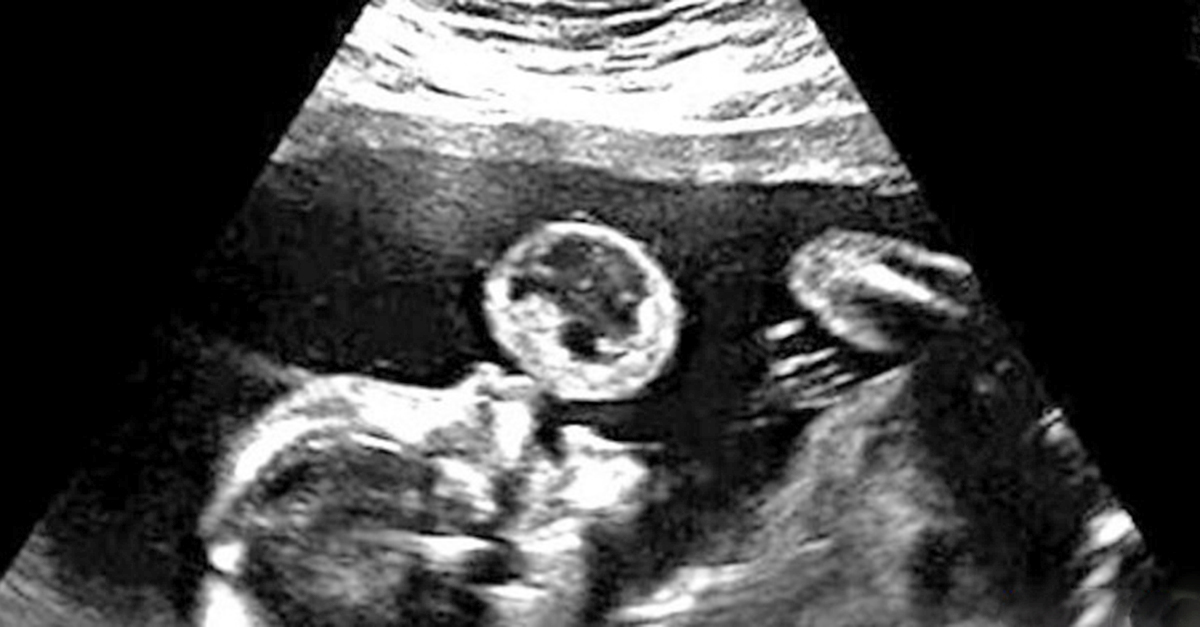

They Thought She Was Blowing A Bubble On The Scan But The Truth Was Frightening

Mom Sees Unborn Baby Blowing Bubble During Ultrasound Doctor Urges Her To Abort Immediately

Woman Thinks Baby Is Blowing A Bubble In Ultrasound Then Doctors Reveal What It Really Is